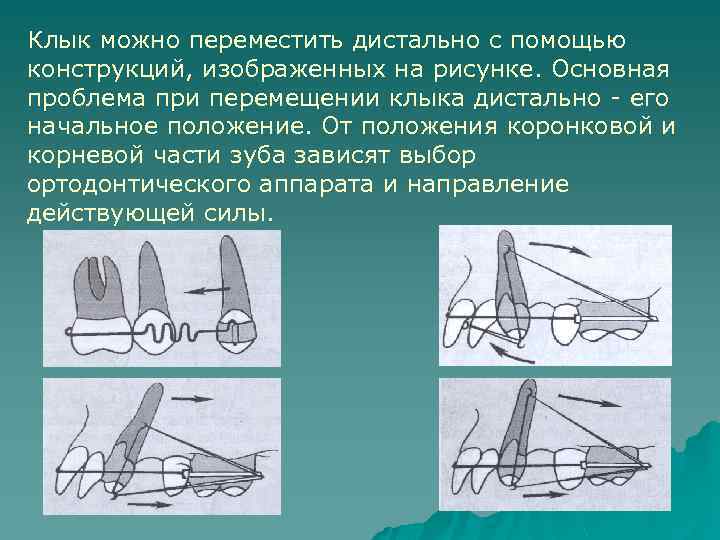

Клык можно переместить дистально с помощью конструкций, изображенных на рисунке. Основная проблема при перемещении клыка дистально - его начальное положение. От положения коронковой и корневой части зуба зависят выбор ортодонтического аппарата и направление действующей силы.